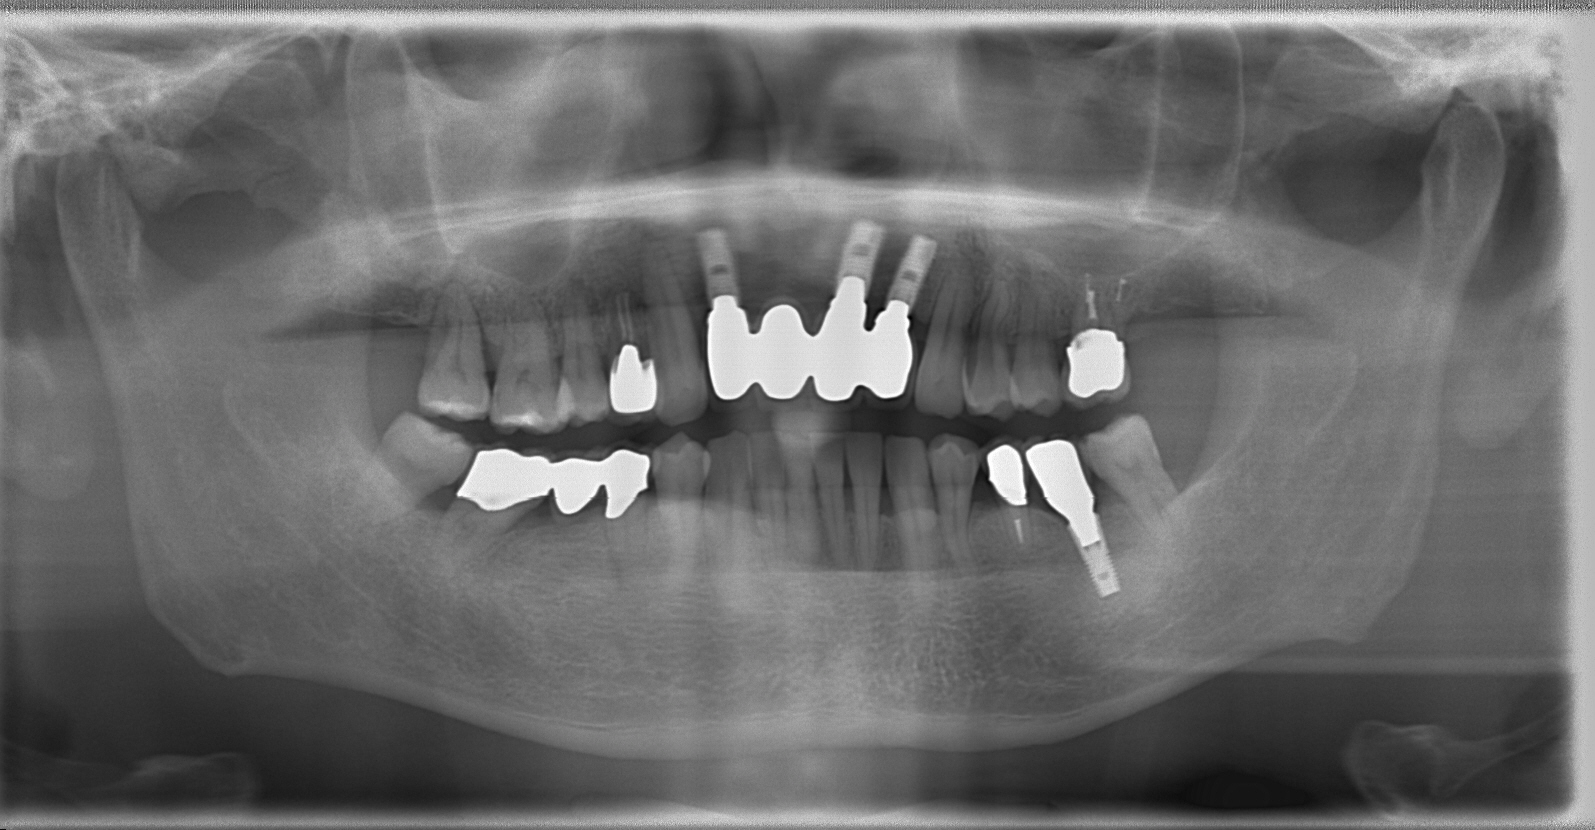

この患者さんは、上顎前歯部4本が根の病気や歯根破折などで抜歯せざるをえなかった方です。

抜歯後は、下の写真のような状態になりました。患者さんは、前歯欠損部に歯を作るために周囲の歯を削りたくないとのことで、インプラント治療を希望されました。

そこで、インプラント手術の前に歯科用CTを撮影すると、予想していた通り、歯槽骨の幅が狭いことがわかりました。

インプラントは、最終的な被せ物の位置を参考に、歯槽骨内に埋入しなければならないため、これでは歯槽骨の適正な位置にインプラントを埋入することができません。

インプラント治療後です。

周囲の歯を削ることなく、噛めるようになりました。現在はメインテナンス中ですが、患者さんのプラークコントロールも非常によく、良好な状態が維持されています。